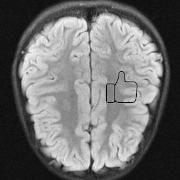

The main consequence of this result is that there is an accuracy-hallucination barrier. If the map ΨΨ\Psi performs too well on a certain image x1subscript𝑥1x_{1} with detail lying close to 𝒩(A)𝒩𝐴\mathcal{N}(A), then it will hallucinate, by incorrectly transferring this detail to another image x2subscript𝑥2x_{2}. Note this situation can arise even when 𝒩(A)={0}𝒩𝐴0\mathcal{N}(A)=\{0\}: if A𝐴A is ill-conditioned then there exist many ‘candidate’ details xDetsubscript𝑥Detx_{\mathrm{Det}} for which AxDet𝐴subscript𝑥DetAx_{\mathrm{Det}} is small while xDetsubscript𝑥Detx_{\mathrm{Det}} is not. In Fig. 2 we demonstrate an example of this effect. A NN is trained to accurately recover a brain image with artificial details. Then when used to reconstruct the detail-free brain image, it hallucinates one of the details. Theorem 4.1 also explains why only one of the details is transferred in this case, and not the other.

xbr+xth+xmisubscript𝑥brsubscript𝑥thsubscript𝑥mix_{\mathrm{br}}+x_{\mathrm{th}}+x_{\mathrm{mi}} xbr+xthsubscript𝑥brsubscript𝑥thx_{\mathrm{br}}+x_{\mathrm{th}} xbrsubscript𝑥brx_{\mathrm{br}}

Refer to caption Refer to caption Refer to caption

Ψ(A(xbr+xth+xmi))Ψ𝐴subscript𝑥brsubscript𝑥thsubscript𝑥mi\Psi(A(x_{\mathrm{br}}+x_{\mathrm{th}}+x_{\mathrm{mi}})) Ψ(A(xbr+xth))Ψ𝐴subscript𝑥brsubscript𝑥th\Psi(A(x_{\mathrm{br}}+x_{\mathrm{th}})) Ψ(Axbr)Ψ𝐴subscript𝑥br\Psi(Ax_{\mathrm{br}})

Refer to caption \begin{overpic}[width=433.62pt]{plots/mod_009_test_im_nbr_004_mod_rec_crop.png} \put(24.0,79.0){\color[rgb]{1,0,0}\definecolor[named]{pgfstrokecolor}{rgb}{1,0,0}\vector(1,-2){6.0}} \end{overpic} \begin{overpic}[width=433.62pt]{plots/mod_009_test_im_nbr_004_rec_crop.png} \put(24.0,79.0){\color[rgb]{1,0,0}\definecolor[named]{pgfstrokecolor}{rgb}{1,0,0}\vector(1,-2){6.0}} \end{overpic}

Figure 2: (Hallucinations due to detail transfer). A trained NN Ψ:mN:Ψsuperscript𝑚superscript𝑁\Psi\colon\mathbb{C}^{m}\rightarrow\mathbb{C}^{N} accurately recovers the detail image in the first column. But it hallucinates by incorrectly transferring the ‘Mickey Mouse’ detail xmisubscript𝑥mix_{\mathrm{mi}} in the first column when recovering the images in the second and third column. The measurement matrix is a subsampled Fourier transform with m/N=20%𝑚𝑁percent20m/N=20\%, which models a MRI acquisition with 555-fold acceleration. See §A for further information on this experiment. Note that the the NN does not transfer the ‘Thumb’ detail xthsubscript𝑥thx_{\mathrm{th}}. Theorems 4.1 and 4.3 shed light on why this is the case.

Fig. 2 presents an example of this result. In this figure, the ‘Mickey Mouse’ detail xmi𝒩(A)subscript𝑥mi𝒩𝐴x_{\mathrm{mi}}\in\mathcal{N}(A), whereas the ‘Thumb’ detail xthsubscript𝑥thx_{\mathrm{th}} has relatively large measurements, i.e., |||Axth|||0\mbox{$|\!|\!|$}Ax_{\mathrm{th}}\mbox{$|\!|\!|$}\gg 0. The NN is trained to recover the image xbr+xth+xmisubscript𝑥brsubscript𝑥thsubscript𝑥mix_{\mathrm{br}}+x_{\mathrm{th}}+x_{\mathrm{mi}}. As a result, it incorrectly transfers the detail xmisubscript𝑥mix_{\mathrm{mi}}, while the detail xthsubscript𝑥thx_{\mathrm{th}} is handled correctly (i.e., it is not transferred). Fig. 4 shows another example of this effect. In this case, A𝐴A is a subsampled Radon transform, which models a CT imaging scenario. Here, the NN is trained to recover the detail image x+xDet𝑥subscript𝑥Detx+x_{\mathrm{Det}}, and as a result, it incorrectly transfer the detail xDetsubscript𝑥Detx_{\mathrm{Det}} when recovering the detail-free image x𝑥x.